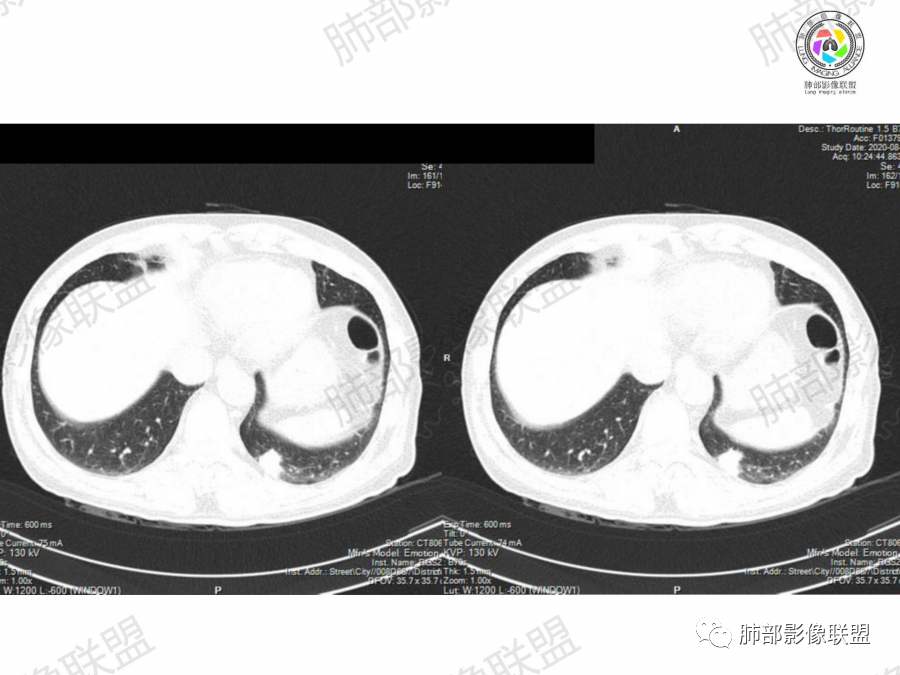

晨读:左肺下叶胸膜下实性结节影边缘毛糙,有毛刺,分叶,近段支气管未见显示,可能堵塞,远端宽基底与胸膜相贴,边缘平直,部分彭隆,病灶局限、单发,无增强,不好判断肿瘤血供,临床男性,63岁,无症状,体检发现,有吸烟史,考虑恶性:腺癌,鳞癌,小细胞肺癌,鉴别:肺隐球菌建议增强及穿刺检查。

晨读病例,老年人 ,吸烟史,左肺下叶结节影,密度均匀,边缘毛糙,周围可见长毛刺,病灶边缘分叶,局部膨隆,部分边界平直,收缩,病灶相邻胸膜处可见糊墙征象,病灶近肺门处见支气管堵塞,考虑恶性病变,周围型肺癌:鳞癌伴肺不张>腺癌,鉴别隐球,炎性假瘤。

细、长、软毛刺

边缘模糊,支气管关系不明确

糊墙,胸膜下脂肪间隙明显增厚

边缘平直为主,部分膨隆,糊墙征

密度比较均匀;

2、影像表现:无肺气肿背景、定位左肺下叶后基底段,不规则结节、与支气管关系不明确,部分边缘平直、部分膨隆,病变与胸膜宽基底相连,病变与胸膜糊墙征,病变周围见细、长、软毛刺,病变密度比较均匀。影像总体倾向炎症、符合肺组织慢性炎症伴机化。

综合分析:

该例病变虽然为老年男性,无肺气肿背景,无临床症状、长软毛刺、刀切边缘、糊墙,病灶密度均匀,周围支气管无截断,病灶密度均匀,基本为良性炎性病变特征,但并不是绝对,工作中应该建议治疗后随访排外其它。